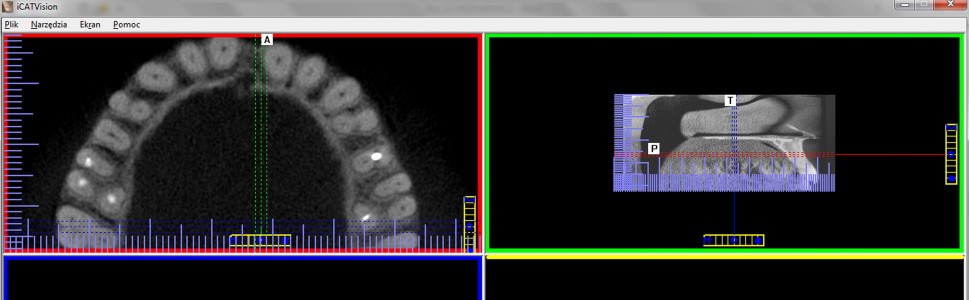

Aby leczenie kanałowe mogło zakończyć się sukcesem, wszystkie kanały korzeniowe powinny zostać dokładnie opracowane i szczelnie wypełnione. Pominięcie któregoś z nich może być przyczyną niewygojenia się, a nawet powstania nowych zmian zapalnych w tkankach okołowierzchołkowych. W uzasadnionych przypadkach, w celu dokładnej oceny morfologii zębów oraz poznania przyczyny niepowodzenia pierwotnego leczenia kanałowego, można zastosować tomografię komputerową wiązki stożkowej (CBCT).

Celem pracy jest opis przypadku ponownego leczenia kanałowego drugiego zęba przedtrzonowego szczęki, w którego diagnostyce wykorzystano badanie CBCT. Dzięki temu udało się wykryć, a następnie właściwie opracować i wypełnić pominięty wcześniej kanał korzeniowy. Ponowne leczenie endodontyczne zakończyło się sukcesem.